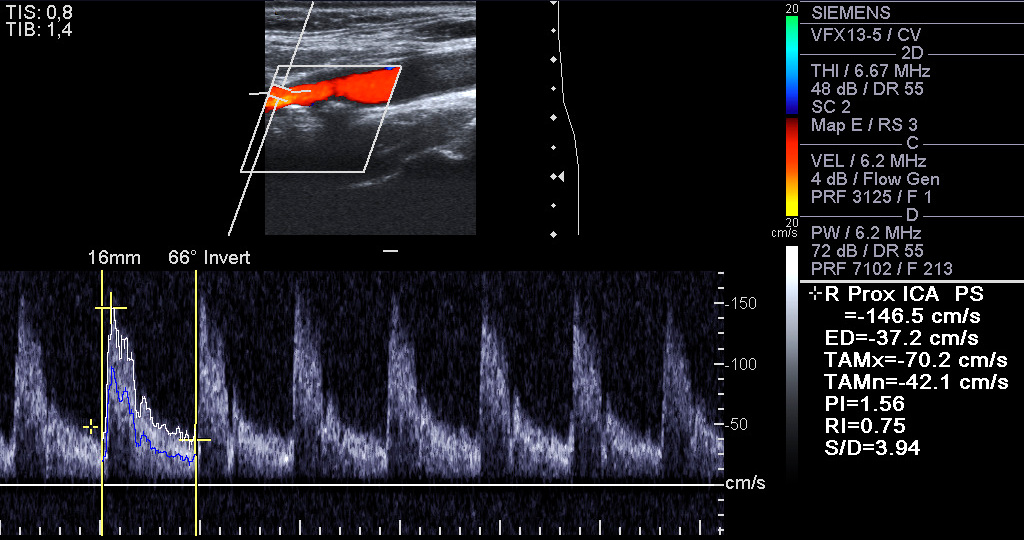

A carotid artery Doppler ultrasound is a diagnostic test used to check the arteries in the neck What Does Plaque In Carotid Artery Look Like Mayo's robust mri protocols facilitate the detection of specific carotid plaque. Carotid arteries become blocked with plaque, a combination of cholesterol, fat, calcium, fibrin, waste products, and other substances that collect on artery walls. Patients in whom carotid artery disease is suspected are usually tested using a carotid doppler ultrasound. Plaque is a mix of fat, calcium, and other substances. What Does Plaque In Carotid Artery Look Like.